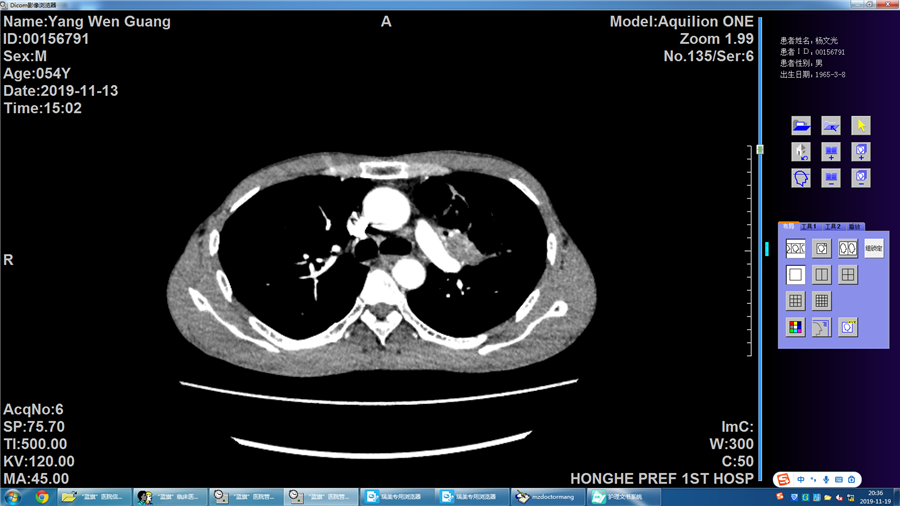

近日,云南省滇南中心医院(红河州第一人民医院)心胸外科团队与麻醉科团队、感染科团队、手术室护理团队、心胸外科护理团队通过多学科协作,采用高难度的支气管-肺动脉双袖式肺叶切除手术方式,为一位54岁男性病人切除了左肺恶性肿瘤,在完整切除肿瘤同时,为患者保住了左肺下叶,为患者的术后恢复、长期预后提供了良好基础。

患者本次入院前已有较长时间的左侧胸痛、胸闷、咳嗽症状,疼痛呈持续性,并逐渐加重,参加轻体力活动即感到胸闷气促,生活质量下降明显。患者及家属意识到病情的严重性,到我院就诊,因为患者曾患肺结核,患者首先到了感染科住院治疗。经过感染科细致的检查,感染科霍松主任带领科室医生讨论后认为,患者不仅存在肺部结核感染的情况,患者极有可能同时存在肺部肿瘤,两种疾病共同导致患者出现上述不适情况。患者目前可能还有最后的手术机会。感染科随即联系了心胸外科会诊。心胸外科会诊医师细致了解病情后,将患者情况在科室讨论会上作了详细介绍,王璟主任同时联系相关科室会诊,讨论中大家认为,患者肿瘤位于肺门位置,且属于肿瘤局部晚期,肿瘤已经侵犯了肺动脉主干及左肺支气管,手术难度大,风险高,有可能不能做到肿瘤的完整切除,如果为了保证肿瘤完整切除而采用传统手术方式,切除整个左肺,结合患者欠佳的肺功能,患者术后极有出现呼吸衰竭等危及生命的情况。

王璟主任提出是否可以尝试采用更高难度的支气管-肺动脉双袖式肺叶切除方式,为患者切除肿瘤原发的上肺的同时,尽可能为患者保留受肿瘤影响较小的下肺。双袖式切除简单来说,就是除了将肿瘤完整切除,同时将受肿瘤侵犯的血管、气管一并切除,再将两端健康的血管、气管做端-端吻合。

11月19日,在麻醉科丁俊主任及其团队以精湛的专业技能的保驾护航下,由李俊副主任医师主刀,心胸外科团队耗时近6小时,为患者完整切除了肺门区的肿瘤及受侵犯的支气管及肺动脉,并作了细致的端-端吻合,成功为患者保住了左肺下叶。